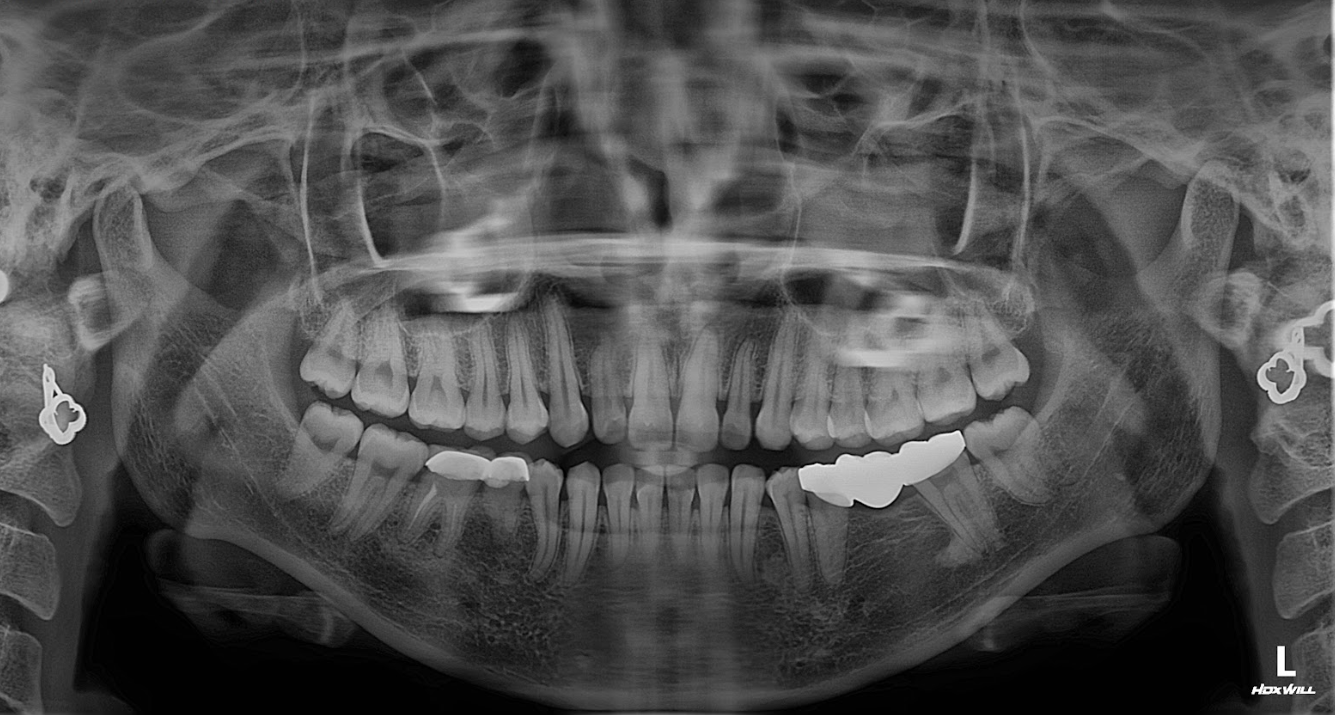

Chị Vân được BS Bùi Văn Hưng trực tiếp thăm khám và thực hiện các bước kiểm tra:

Chụp CT Conebeam 3D để đánh giá tình trạng xương hàm.

Kiểm tra răng trụ đã mài làm cầu → phát hiện có dấu hiệu sâu ngầm và viêm lợi nhẹ.

Đánh giá mật độ xương tại vị trí răng mất → đủ điều kiện cấy Implant, không cần ghép xương.